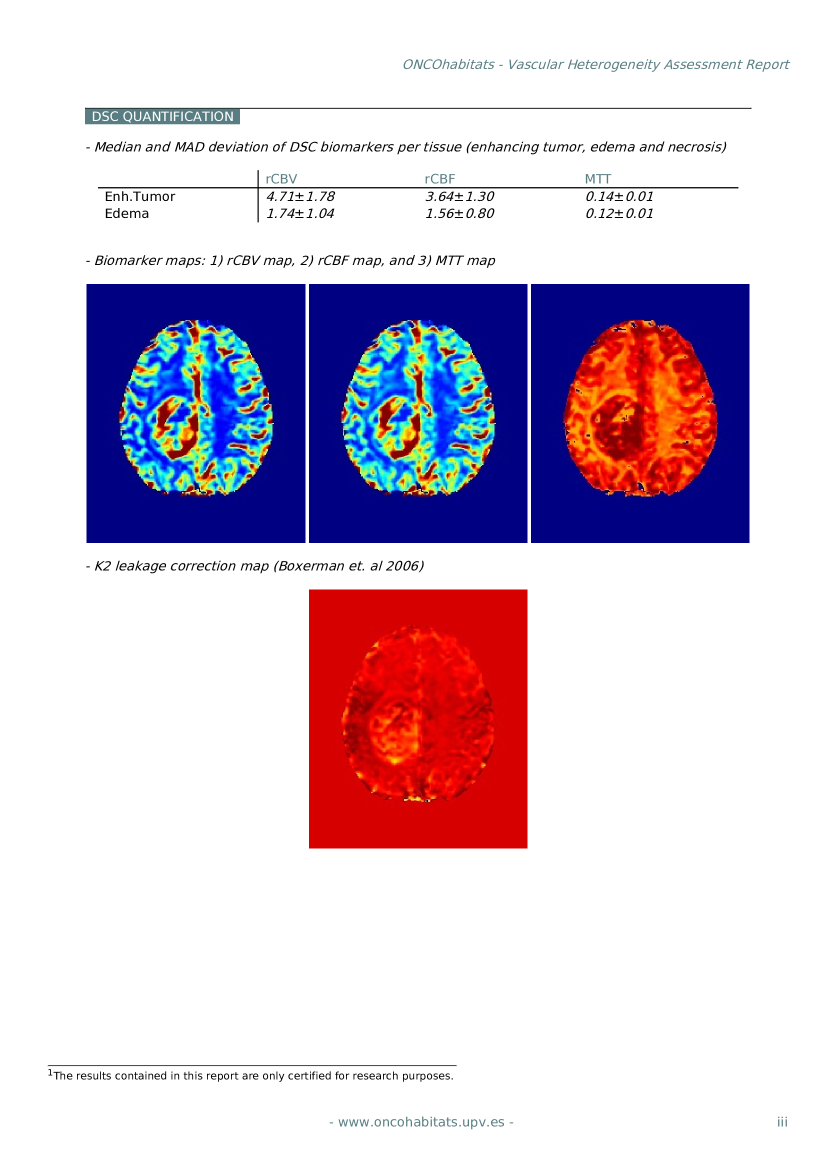

Finally, the methods and technology developed in this thesis have been integrated into an online public open-access platform for its academic use. The ONCOhabitats platform is hosted at https://www.oncohabitats.upv.es, and provides two main services: 1) glioblastoma tissue segmentation, and 2) vascular heterogeneity assessment of glioblastomas by means of the HTS method. Both services, in addition to preprocessed images and segmentation maps, automatically generate a radiological report, summarizing the findings of the study. ONCOhabitats not only offers the scientific and medical community access to leading-edge algorithms for the analysis of these tumors, but gives access to its computational cluster capable to process about 300 cases per day.

An online open-access system for glioblastoma MRI analysis

This contribution consists of the development of a web-based system for the analysis of glioblastomas by means of MRI. The system, named ONCOhabitats (https://www.oncohabitats.upv.es), provides free access to all the methods developed and validated in this thesis, but also to other state-of-the-art algorithms in the field of medical image analysis, to offer a complete solution for the study of glioblastoma from raw unprocessed MRI. ONCOhabitats implements two main services to describe the morphological and vascular heterogeneity of the glioblastoma, generating for each service an automated -based report summarizing all the findings of the study. The details of the system were presented in the journal contribution P8 and conference contribution P9, and the software was registered in the technological catalogue of the UPV, as shown in contributions S1 and S2.